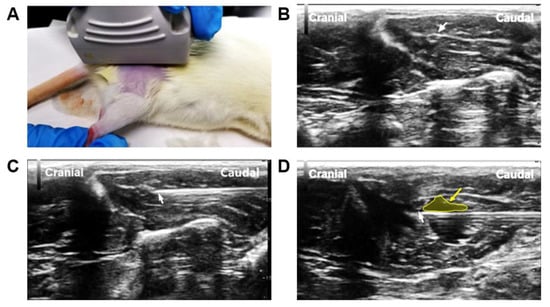

3.1. Assessment of Pain and Neuroma Formation